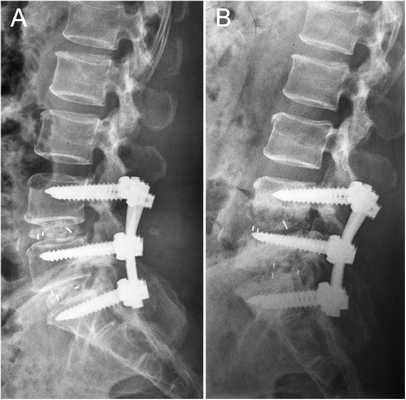

Декомпрессионная операция на поясничном отделе

До недавнего времени оптимальным методом лечения спинального стеноза считалась декомпрессивная ламинэктомия с фиксацией позвонков передними или задними системами стабилизации. Однако установка конструкций приводит к нарушению биомеханики соседних позвоночно-двигательных сегментов и развивается «болезнь смежного уровня», включающая спондилолистез, сколиоз, стеноз позвоночного канала и т.д.

Ученые начали разрабатывать конструкции динамической стабилизации. Сегодня в клинической практике широко применяются фиксирующие системы Dynesys и U-образные межостистые спейсеры. Их установка позволяет добиться лучших функциональных результатов и существенно сократить период реабилитации.

После декомпрессии хирурги выполняют стабилизацию позвоночника. Это помогает зафиксировать позвонки в нужном положении и предупредить их смещение в будущем. Это позволяет избежать вторичного стеноза и нестабильности в позвоночно-двигательных сегментах.